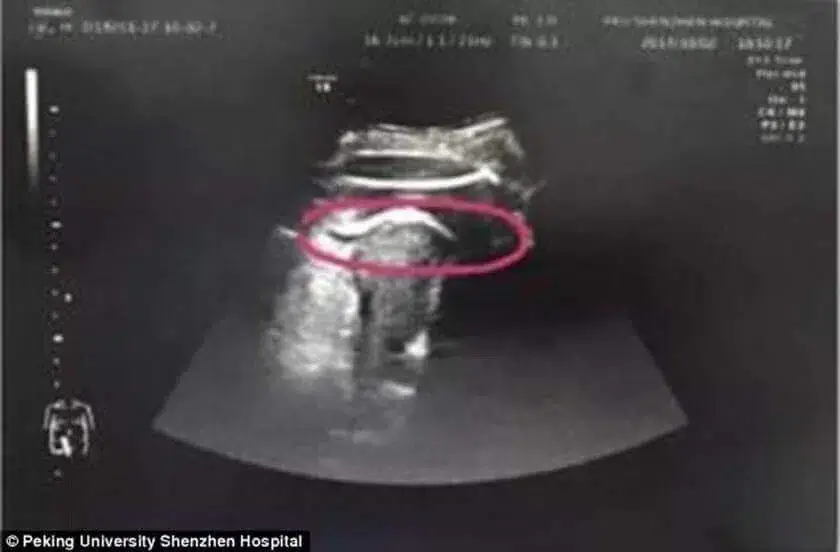

Após vários exames, os especialistas constataram que o bebé a golpeou tão forte que “rasgou” a parede do útero. Imediatamente, a mãe foi levada para a sala de cirurgia e teve de passar por uma cesárea.

De acordo com a assessoria de imprensa do Perking University Shenzhen Hospital, os médicos acharam, primeiramente, que se tratava de algum problema no sistema urinário. Após os exames, constataram o furo no útero.